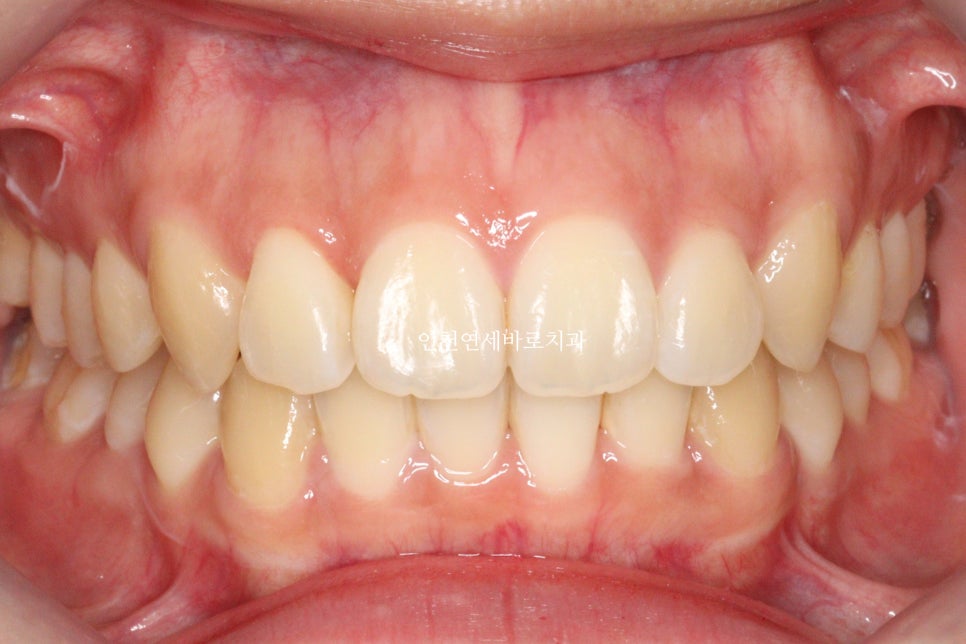

2년 후 역시 잘 유지되고 있으며

긴밀한 교합과 배열로 잘 유지되고 있다고 판단됩니다.